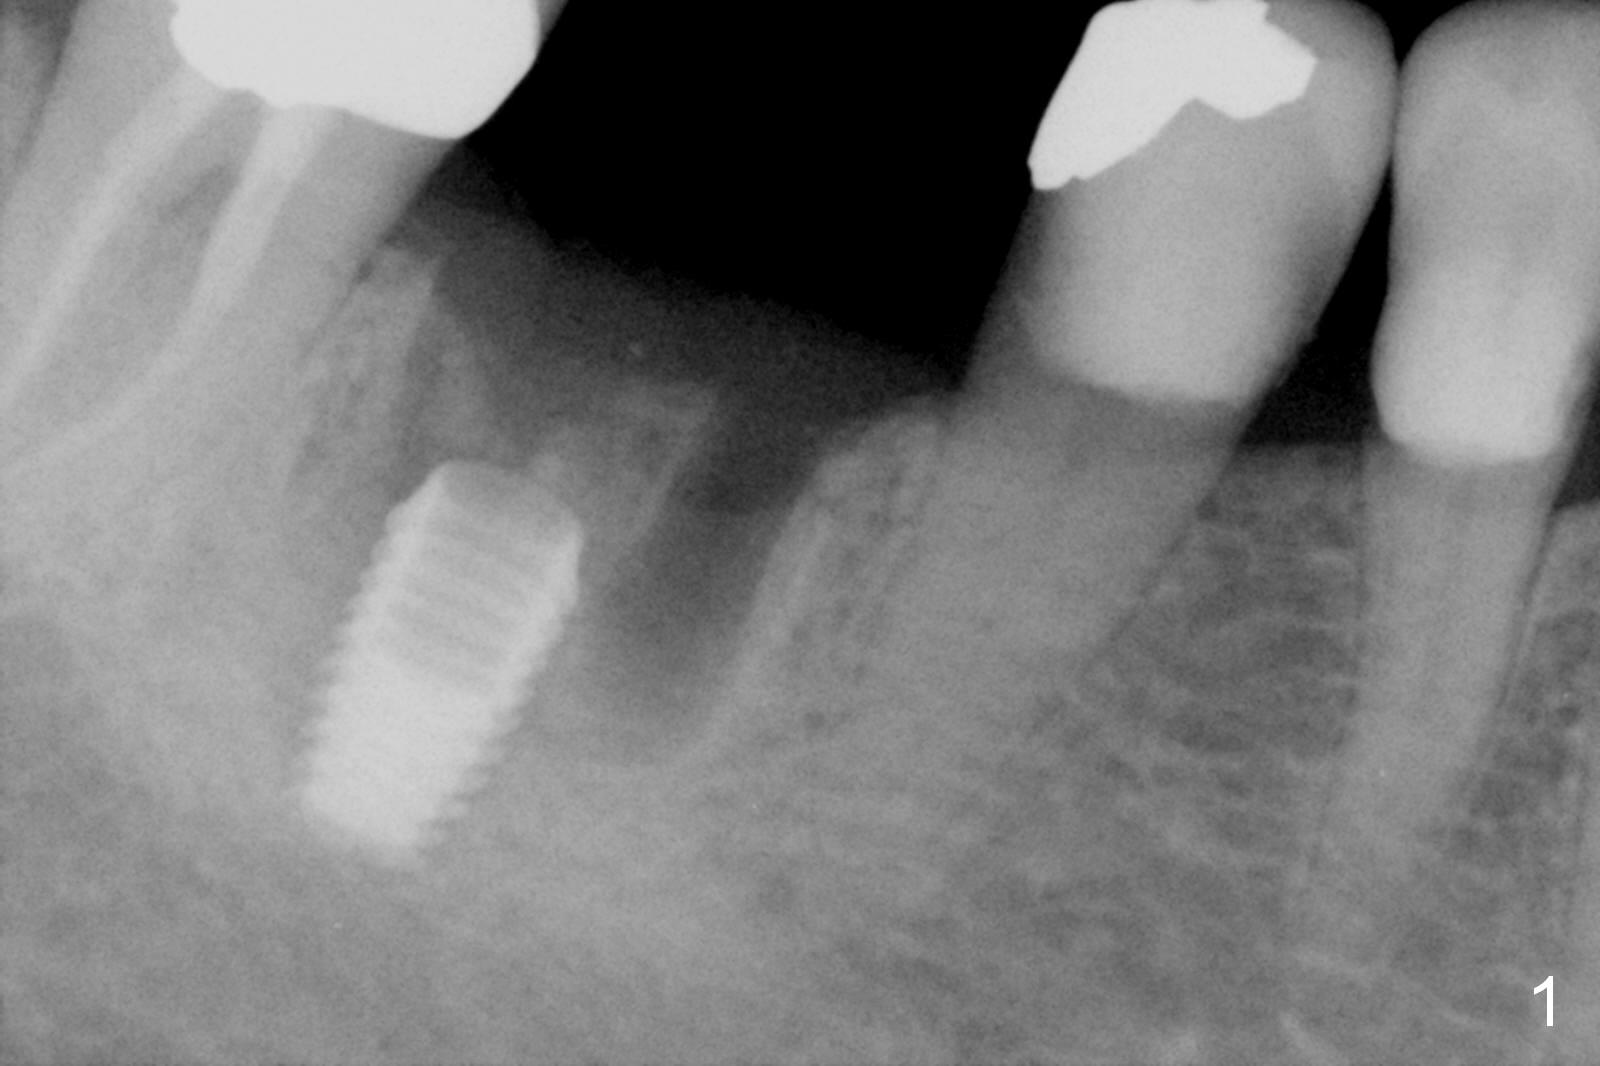

A 74-year-old woman with history of osteoporosis treatment had panoramic X-ray taken 7.5 years post cementation (Fig.2), eight years post Bicon implant placement (Fig.1). Bone density increases around the implant 9 years 7 months post cementation (Fig.3).